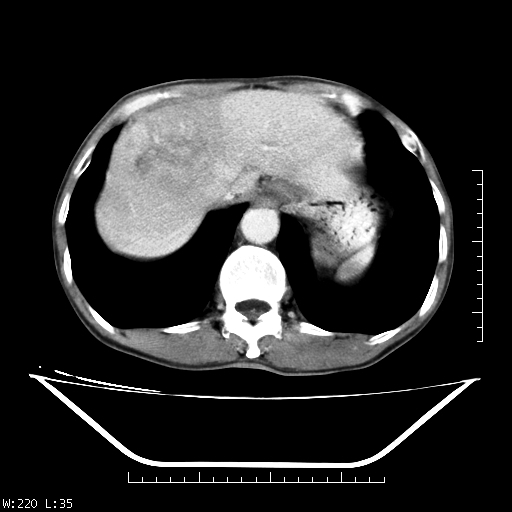

男,70,右上腹痛两月,有乙肝病史,b超提示肝占位,ct如下,请会诊。

补充:该患者afp9.24

肝右叶类圆型密度减低影,密度不均,边界清晰其内可见更低密度影,腹膜后可见小淋巴结肿大,增强扫描动脉期病灶明显强化,静脉期及延时扫描见强化不明显,快进快出表现。

1.肝右叶低密度影考虑为肝癌;

2.肝转移待除外。

平扫呈低密度占位,动脉期斑片状明显强化,病灶边缘清晰,见假包膜;门脉期呈低密度,符合肝癌快进快出强化特征

补充:该患者afp 9.24,似乎与原发性肝癌不符合,另胰头区结构正常吗?请大家继续发表高见。